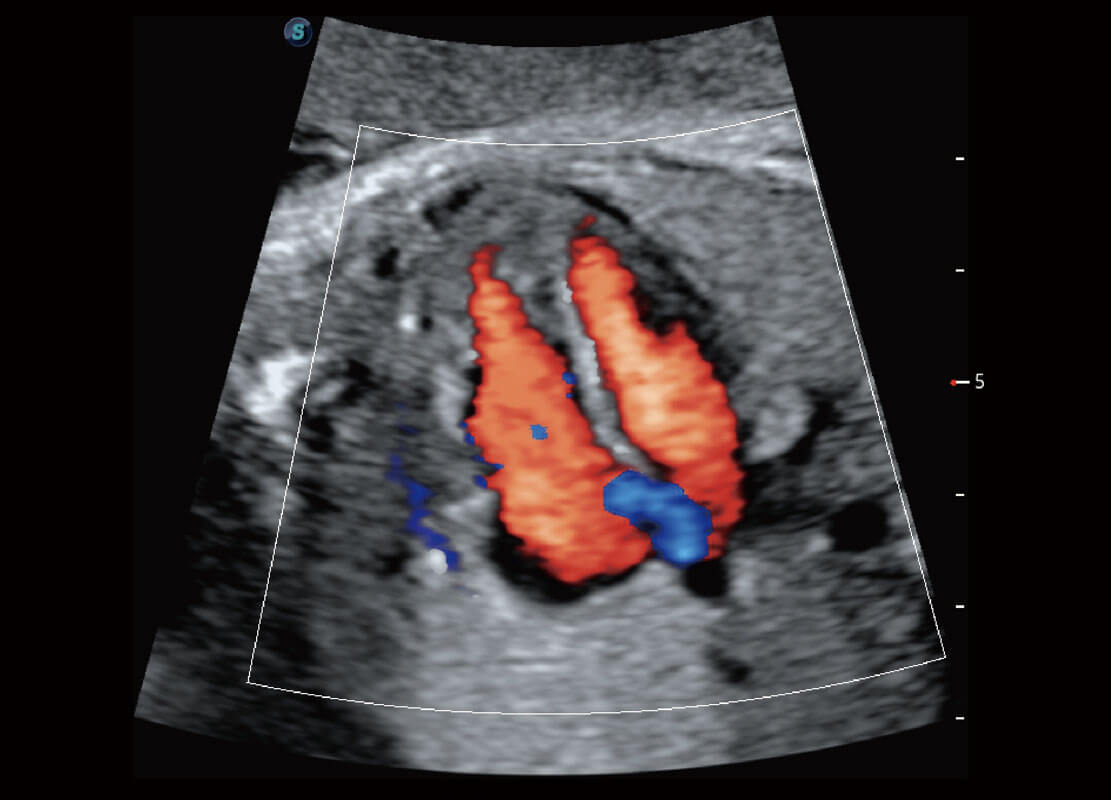

胎儿体循环

四腔切面

四腔心血流

右室双出口